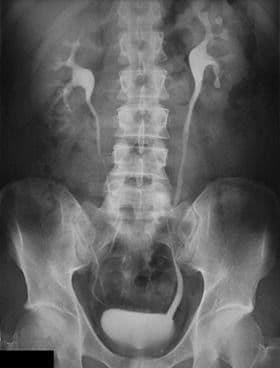

Hysterosalpingography) د.احمد مظفر السعيدي اخصائي الاشعه والسونار

تصوير الرحم بالصبغة<br /><br />تصوير الرحم والبوق (HSG) هو اختبار أشعة سينية لتتبع الشكل الداخلي للرحم والتأكد من انسداد أُنبوبَيْ فالوب.<br />خلال تصوير الرحم والبوق، يتم تمرير أنبوب رفيع خلال المهبل وعنق الرحم. يتم حقن الرحم بصبغة تُعرف بمادة التبايُن.<br />ويتم أخذ عدة صور بالأشعة السينية أو ما يسمى بالتنظير التألقي لتتبع الصبغة. في صورة الأشعة، تظهر الصبغة بيضاء وهي تتدفق إلى الرحم ثم إلى الأنبوبين. إذا كان هنالك شذوذ في شكل الرحم، فسيظهر شكله.<br />إذا كان الأنبوب سالكاً، فسوف تملؤه الصبغة تدريجيا. وتتسرب الصبغة إلى جوف الحوض، حيث يقوم الجسم بامتصاصها.<br /><br />تصوير الجهاز البولي من خلال التصوير المقطعي المحوسب (CT):<br /><br />التصوير المقطعي المحوسب للجهاز البولي هو اختبار تصويري يُستخدم لتقييم المسالك البولية. وتشمل المسالك البولية الكلى والمثانة والأنابيب (الحالبين) التي تنقل البول من الكلى إلى المثانة.<br />يستخدم التصوير المقطعي المحوسب للجهاز البولي الأشعة السينية لتكوين صور متعددة لشريحة من المنطقة التي تتم دراستها في الجسم، بما في ذلك العظام والأنسجة الرخوة والأوعية الدموية. ثم يتم إرسال هذه الصور إلى جهاز كمبيوتر وإعادة بنائها بسرعة إلى صور مفصلة ثنائية الأبعاد.